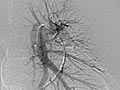

La angiografía pulmonar es una radiografía que utiliza un tinte especial y una cámara (fluoroscopia) para tomar imágenes del flujo sanguíneo en los vasos sanguíneos de los pulmones.

La angiografía pulmonar se usa para evaluar las arterias que van a los pulmones (arterias pulmonares) y los vasos sanguíneos en los pulmones. También puede detectar el estrechamiento o la obstrucción de un vaso sanguíneo que reduce o detiene el flujo de sangre.

Una vez que se haya colocado el catéter, se inyecta el material de contraste a través de él. Es posible que se le pida que inhale y contenga la respiración durante varios segundos. Se tomarán varias imágenes radiográficas, una tras otra. Estas estarán disponibles de inmediato para que su médico pueda observarlas. Debe permanecer muy quieto para que las imágenes sean nítidas. A veces, solo se estudia un pulmón, o se puede repetir el proceso más de una vez para cada pulmón.

La angiografía pulmonar es una radiografía que utiliza un tinte especial y una cámara (fluoroscopia) para tomar imágenes del flujo sanguíneo en los vasos sanguíneos de los pulmones. Es posible que su médico le comunique algunos resultados inmediatamente después de la prueba. Por lo general, los resultados completos están listos el mismo día.

El material de contraste fluye en forma pareja a través de los vasos sanguíneos. |

No se observa estrechamiento, obstrucción, abultamiento ni otro problema en los vasos sanguíneos. Las presiones arteriales pulmonares son normales. |